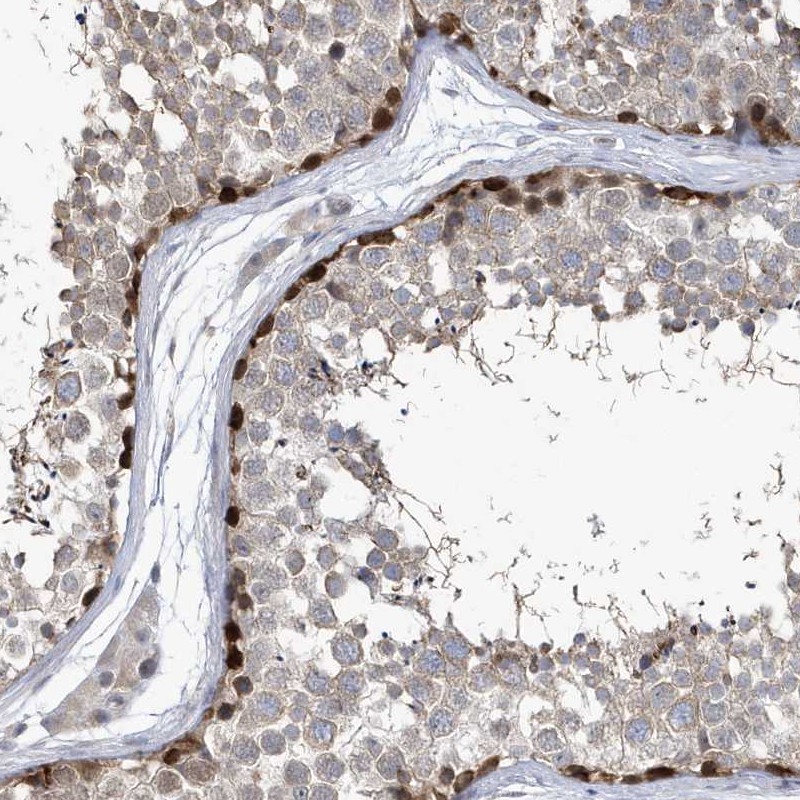

Immunohistochemical staining of human testis shows strong nuclear positivity in a subset of seminiferous ducts cells .